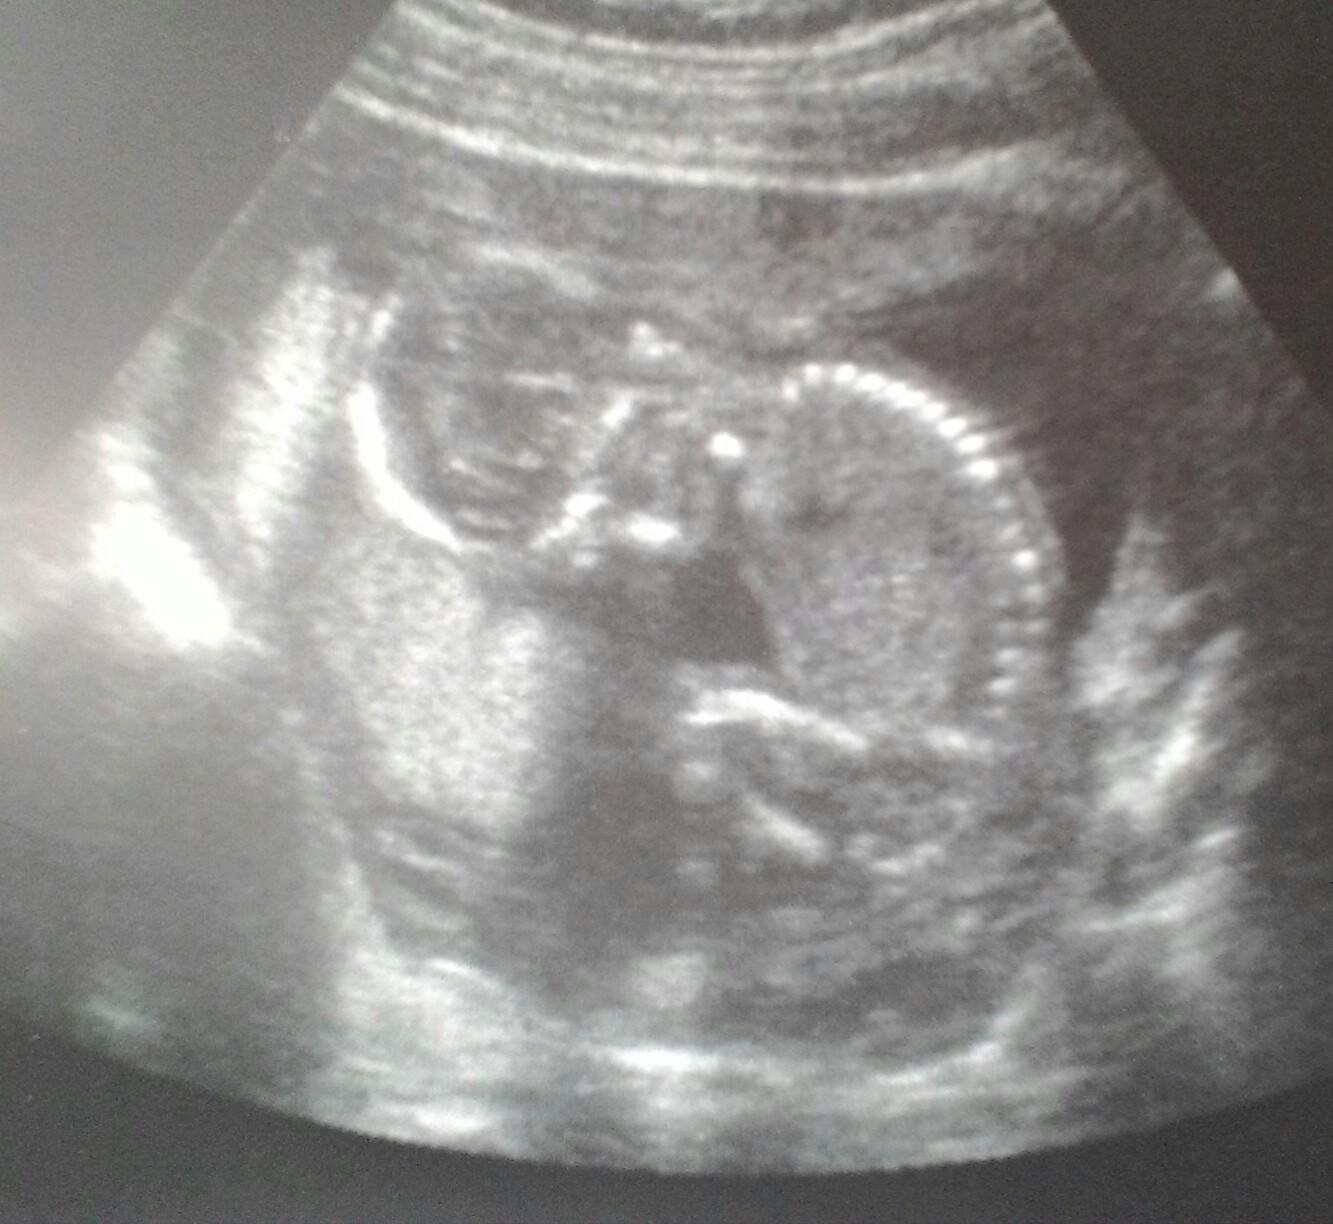

Takze termin pôrodu mame 21.3.19. Zajtra triple a 3D tesim sa a som nedockava aké babo bude a či je v poriadku čo sa tváričky týka. Ešte pohlavie by som rada vediet hehe ❤️❤️❤️💙💙💙

Ja zajtra začínam 16+0 a doteraz som mala len klasický usg. Pre Triple testy volám v pondelok. Dúfam budú v poriadku. Ja mam termín 1.3.

Baby koľko vám meria malé? Ešte mi merala po zadoček a to v 15+3 a malé malo 9,5 cm. Mohlo by mať o 2 cm viac, ale dr povedala ze je v poriadku. ❤️❤️